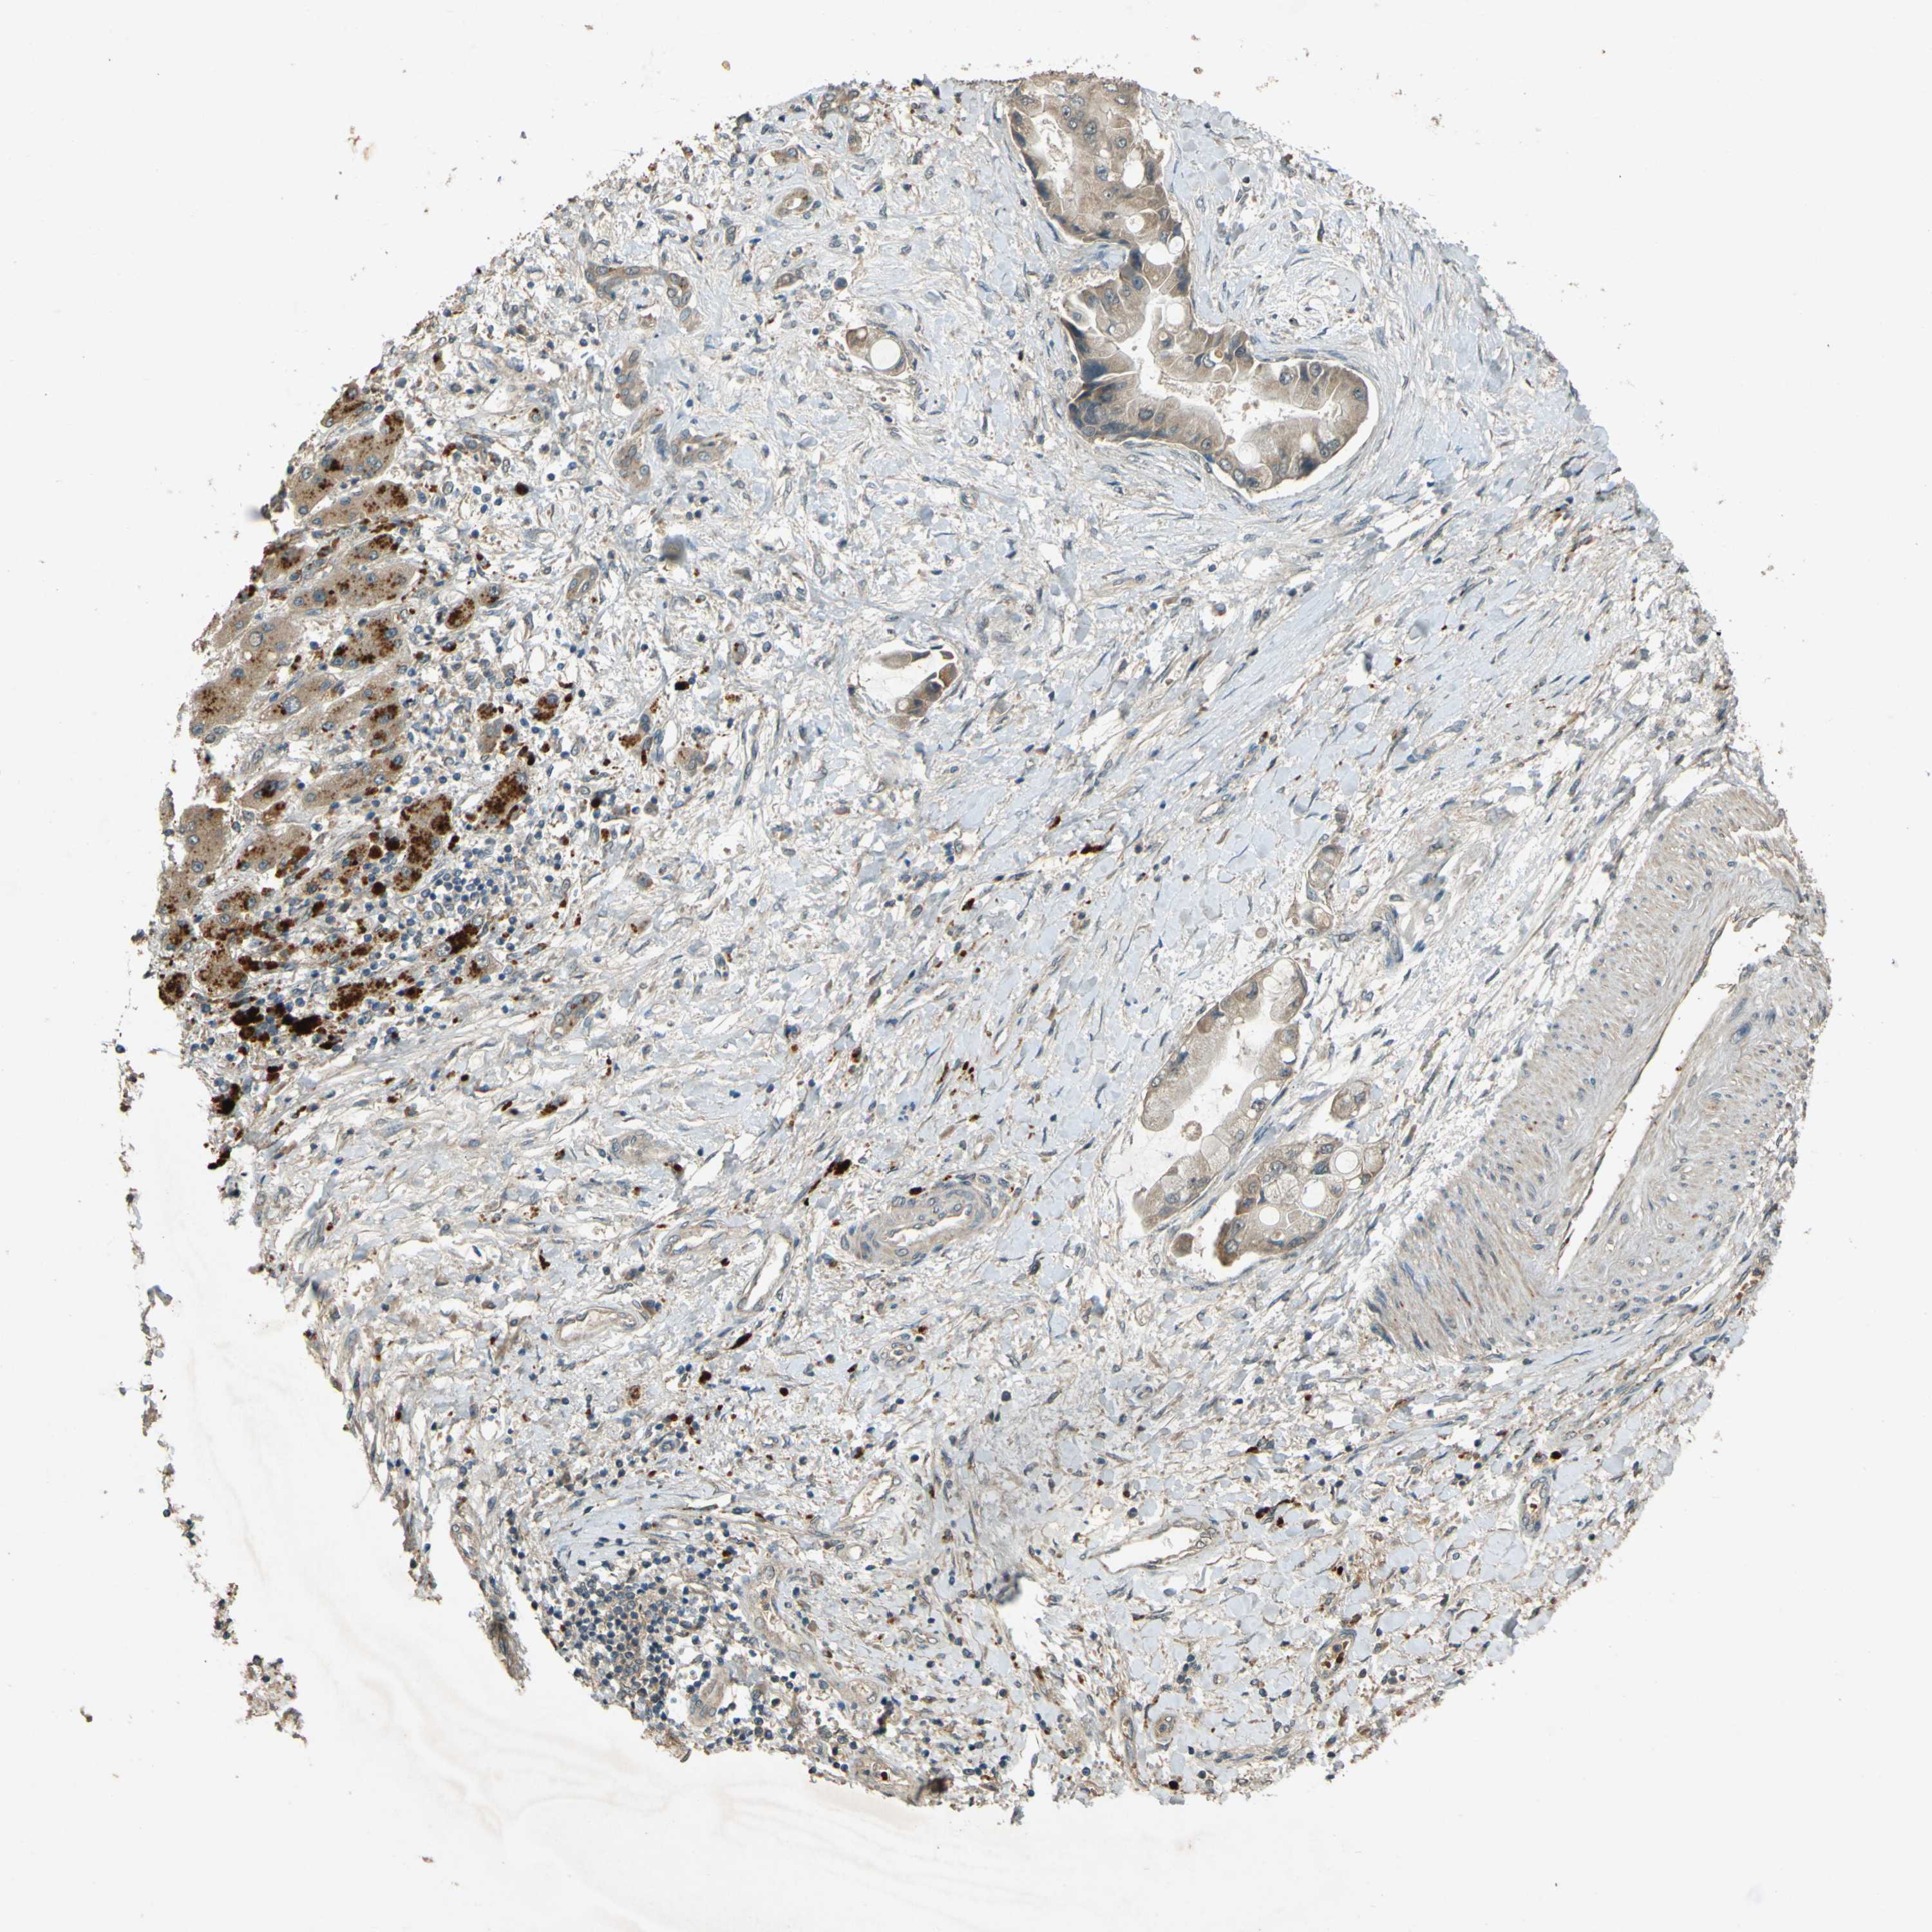

LIVER CANCER - Protein expressioni

A mouse-over function shows sample information and annotation data. Click on an image to view it in a full screen mode. Samples can be filtered based on level of antibody staining by selecting one or several of the following categories: high, medium, low and not detected. The assay and annotation is described here.

Note that samples used for immunohistochemistry by the Human Protein Atlas do not correspond to samples in the TCGA dataset.

Antibody stainingi

Antibody staining in the annotated cell types in the current human tissue is reported as not detected, low, medium, or high, based on conventional immunohistochemistry profiling in selected tissues. This score is based on the combination of the staining intensity and fraction of stained cells.

Each image is clickable and will lead to virtual microscopy that enables deeper exploration of all samples and also displays staining intensity scores, fraction scores and subcellular localization as well as patient and tissue information for each sample.

Antibody HPA020255

Antibody HPA026686

Antibody CAB013512

Staining

High

Medium

Low

Not detected

Intensity

Strong

Moderate

Weak

Negative

Quantity

>75%

75%-25%

<25%

None

Location

Nuclear

Cytoplasmic/membranous

Cytoplasmic/membranous,nuclear

Cholangiocarcinoma

Carcinoma, Hepatocellular, NOS